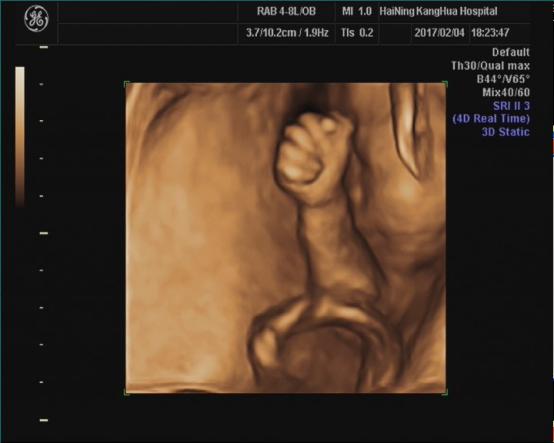

海宁康华医院“胎儿三维彩超检查”,为您创造“透视”条件!

胎儿三维超声检查最佳时间:

22—24周(备注:双胎不做三维超声检查)